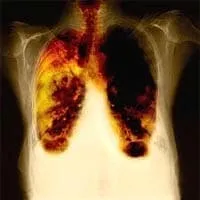

Рак легких — опасное и агрессивное заболевание, которое нередко не удается вылечить из-за слишком быстрого протекания. Давно известно, что курение повышает риск развития рака легких, поэтому этот вид рака так и называют — болезнь курильщика.